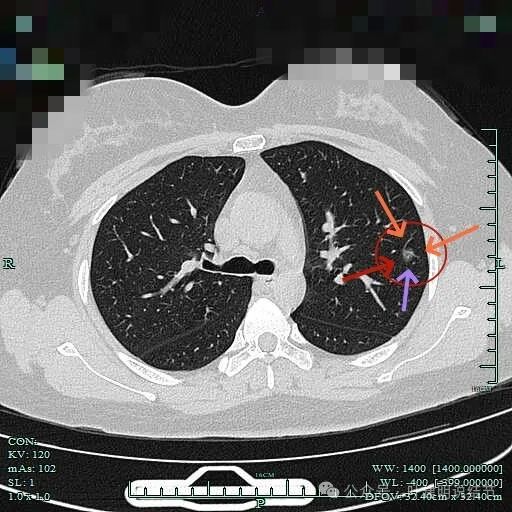

见明显血管进入以及血管穿行于病灶内,边缘有细毛刺征,整体轮廓较为清楚。

血管贴边走行,并形成血管弯征。灶内密度略不均。

血管改变走行,边缘毛刺。